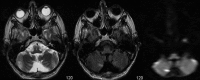

A 48-year-old man was admitted for workup of stroke-like symptoms and generalised tonic-clonic seizures. History and examination revealed that the patient had background diagnoses of type 2 diabetes mellitus, epilepsy and had suffered a temporal lobe infarct 3 years ago. The unusual presentation and physical findings, along with subsequent MRI findings led to a diagnosis of mitochondrial myopathy, encephalopathy, lactic acidosis and stroke-like episodes (MELAS). MELAS is a mitochondrial disorder typified by the aforementioned symptoms, and is typically diagnosed in the first two decades of life.